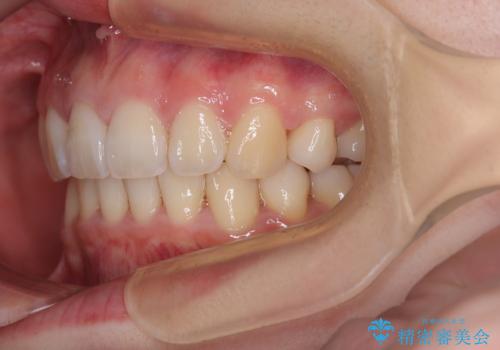

飛び出した上顎前歯 抜歯矯正でスッキリとした横顔に

- 下唇に跡がつくほどに飛び出した上顎前歯を気にして来院された患者様です。

来院された時から4本の抜歯が必要であることを理解されていらしており、通法通り上下左右の第一小臼歯4本を抜歯し、ワイヤー装置にて矯正治療を行うこととしました。

順調に治療が進み、2年弱で想定していたとおりの仕上がりにて治療を終えることができました。